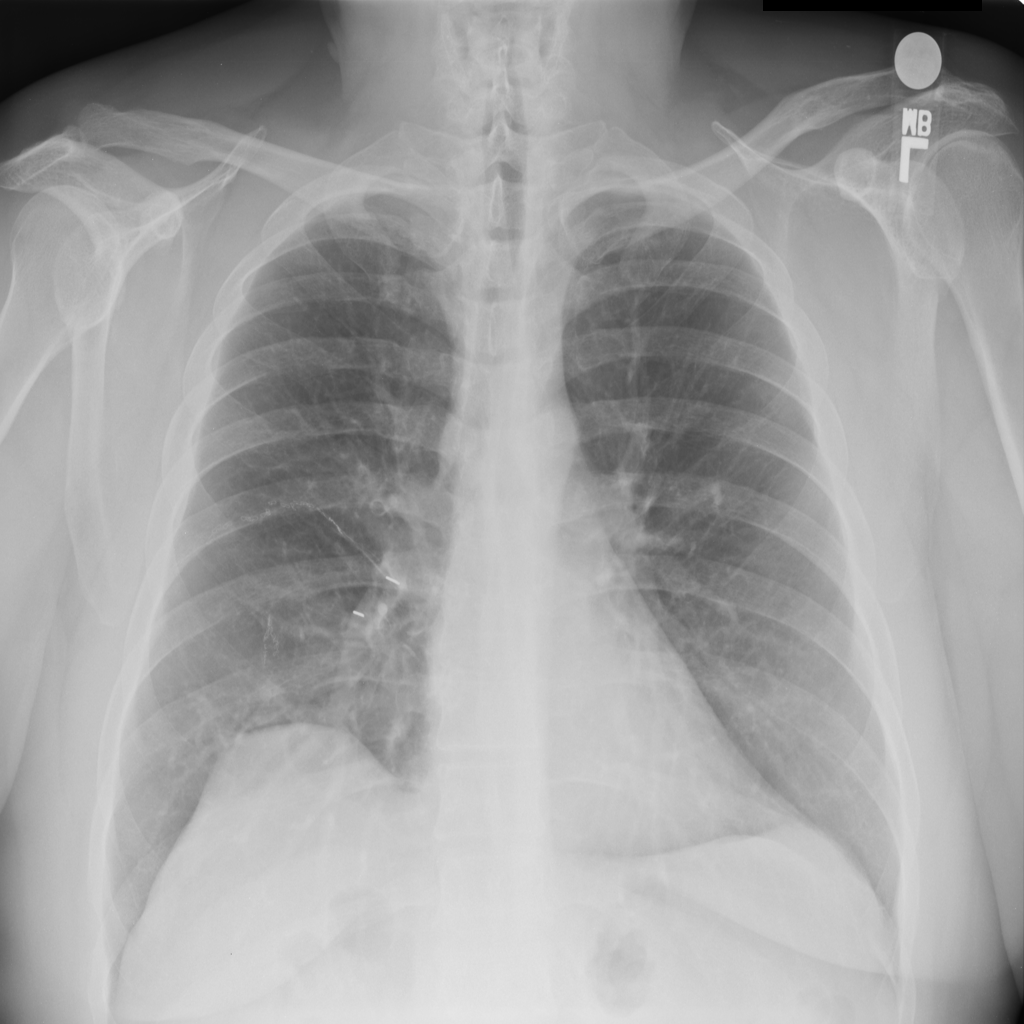

PAT-86C8 · IMG-006Atelectasis

PAT-86C8 · IMG-006

PA